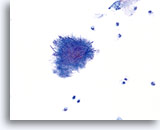

Postpartum

HSIL in a postpartum sample. Note the increased N/C ratio and abnormal chromatin in the HSIL cells as compared to the parabasal cells, apparent even at low magnification.

20X